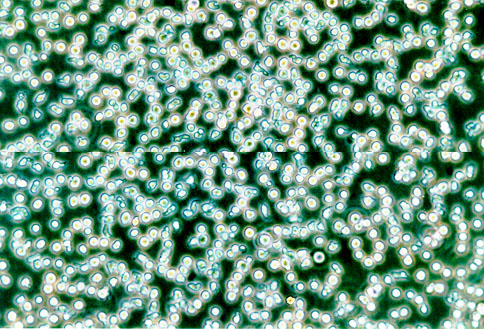

形态特征 淋巴母细胞样

生长特征 悬浮